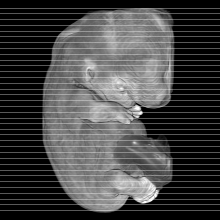

Carnegie Stage 19 (47 post-ovulatory days)

Most embryos at stage 19 are approximately 47-48 post-ovulatory days old and measure 17-20 mm in length. Distinguishing criteria for this stage include straightening of the trunk, the limbs extend nearly directly forward, toe rays are prominent, but interdigital notches have not yet appeared in the foot.

Although some of the photographs below show abnormal embryos, the animations and MRI slice images all depict normal embryos. Abnormal embryos are noted in the titles of the large photos when they are opened.